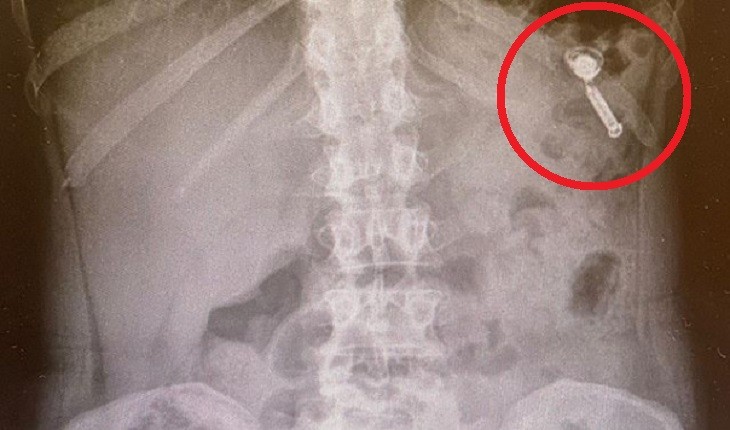

Famosa Chef da TV engole fone de ouvido achando que era remédio; raio-x mostra tudo

Apesar do susto, a gastrônoma e apresentadora disse para os seguidores que passa bem.